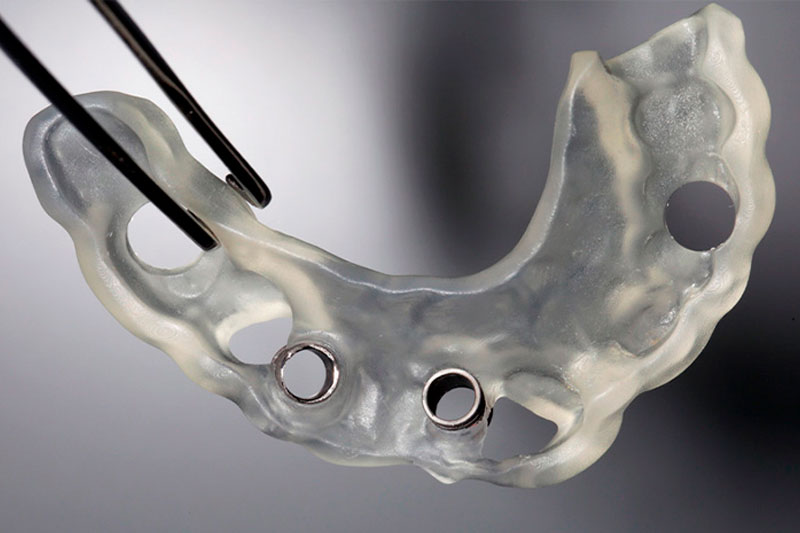

A Oliver Coll, cirurgia guiada per ordinador:

Precisió i seguretat en cada cas.

En aquells casos en què està indicat, utilitzem cirurgia guiada per ordinador. Mitjançant una planificació digital prèvia i una guia quirúrgica dissenyada a mida per a cada pacient, podem col·locar els implants amb una precisió mil·limètrica, respectant l’anatomia de cada persona. Aquesta tècnica millora la seguretat del procediment, fa la intervenció menys invasiva i afavoreix una recuperació més ràpida i còmoda.